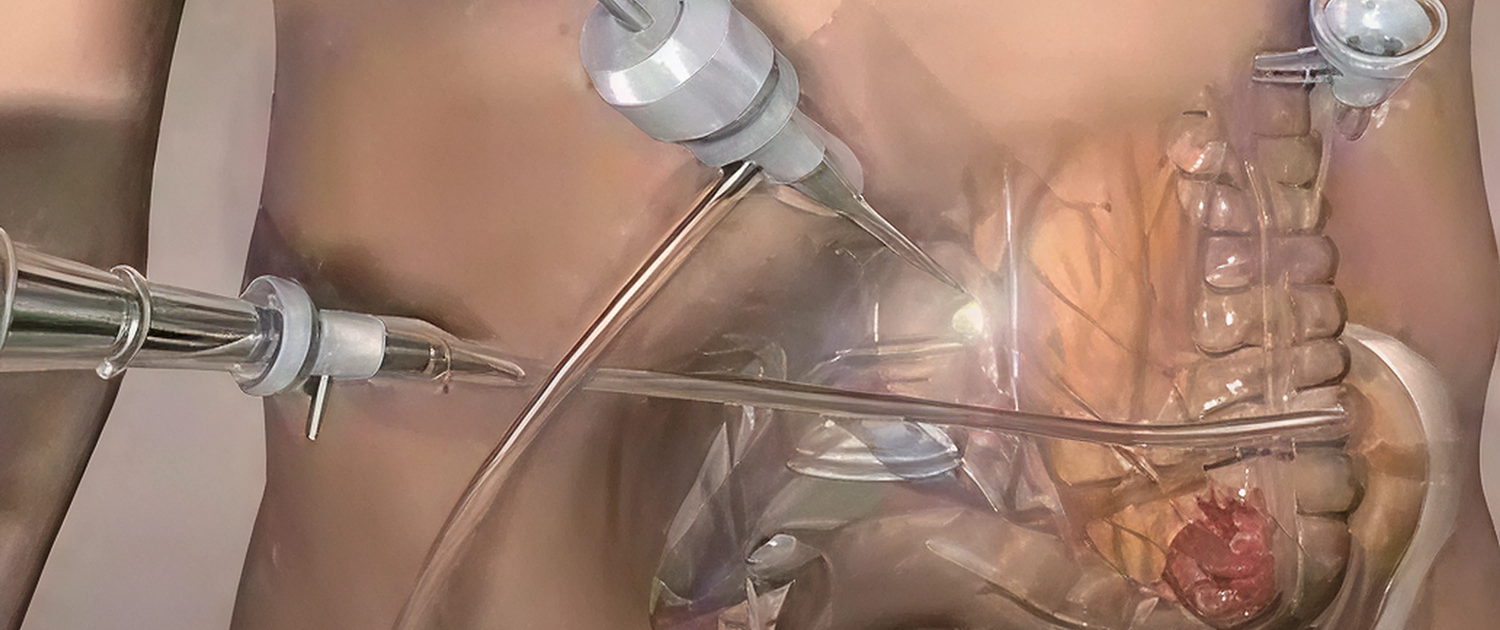

Laparoscopic colorectal surgery is a minimally invasive approach used to treat conditions affecting the colon, rectum, and lower digestive tract. At Gastroheal, we offer advanced laparoscopic colorectal procedures designed to provide precise treatment with reduced surgical trauma and faster recovery.

Minimally Invasive Technique

Smaller incisions resulting in less pain and scarring.

Enhanced Surgical Accuracy

High-definition visualization for precise colorectal procedures.